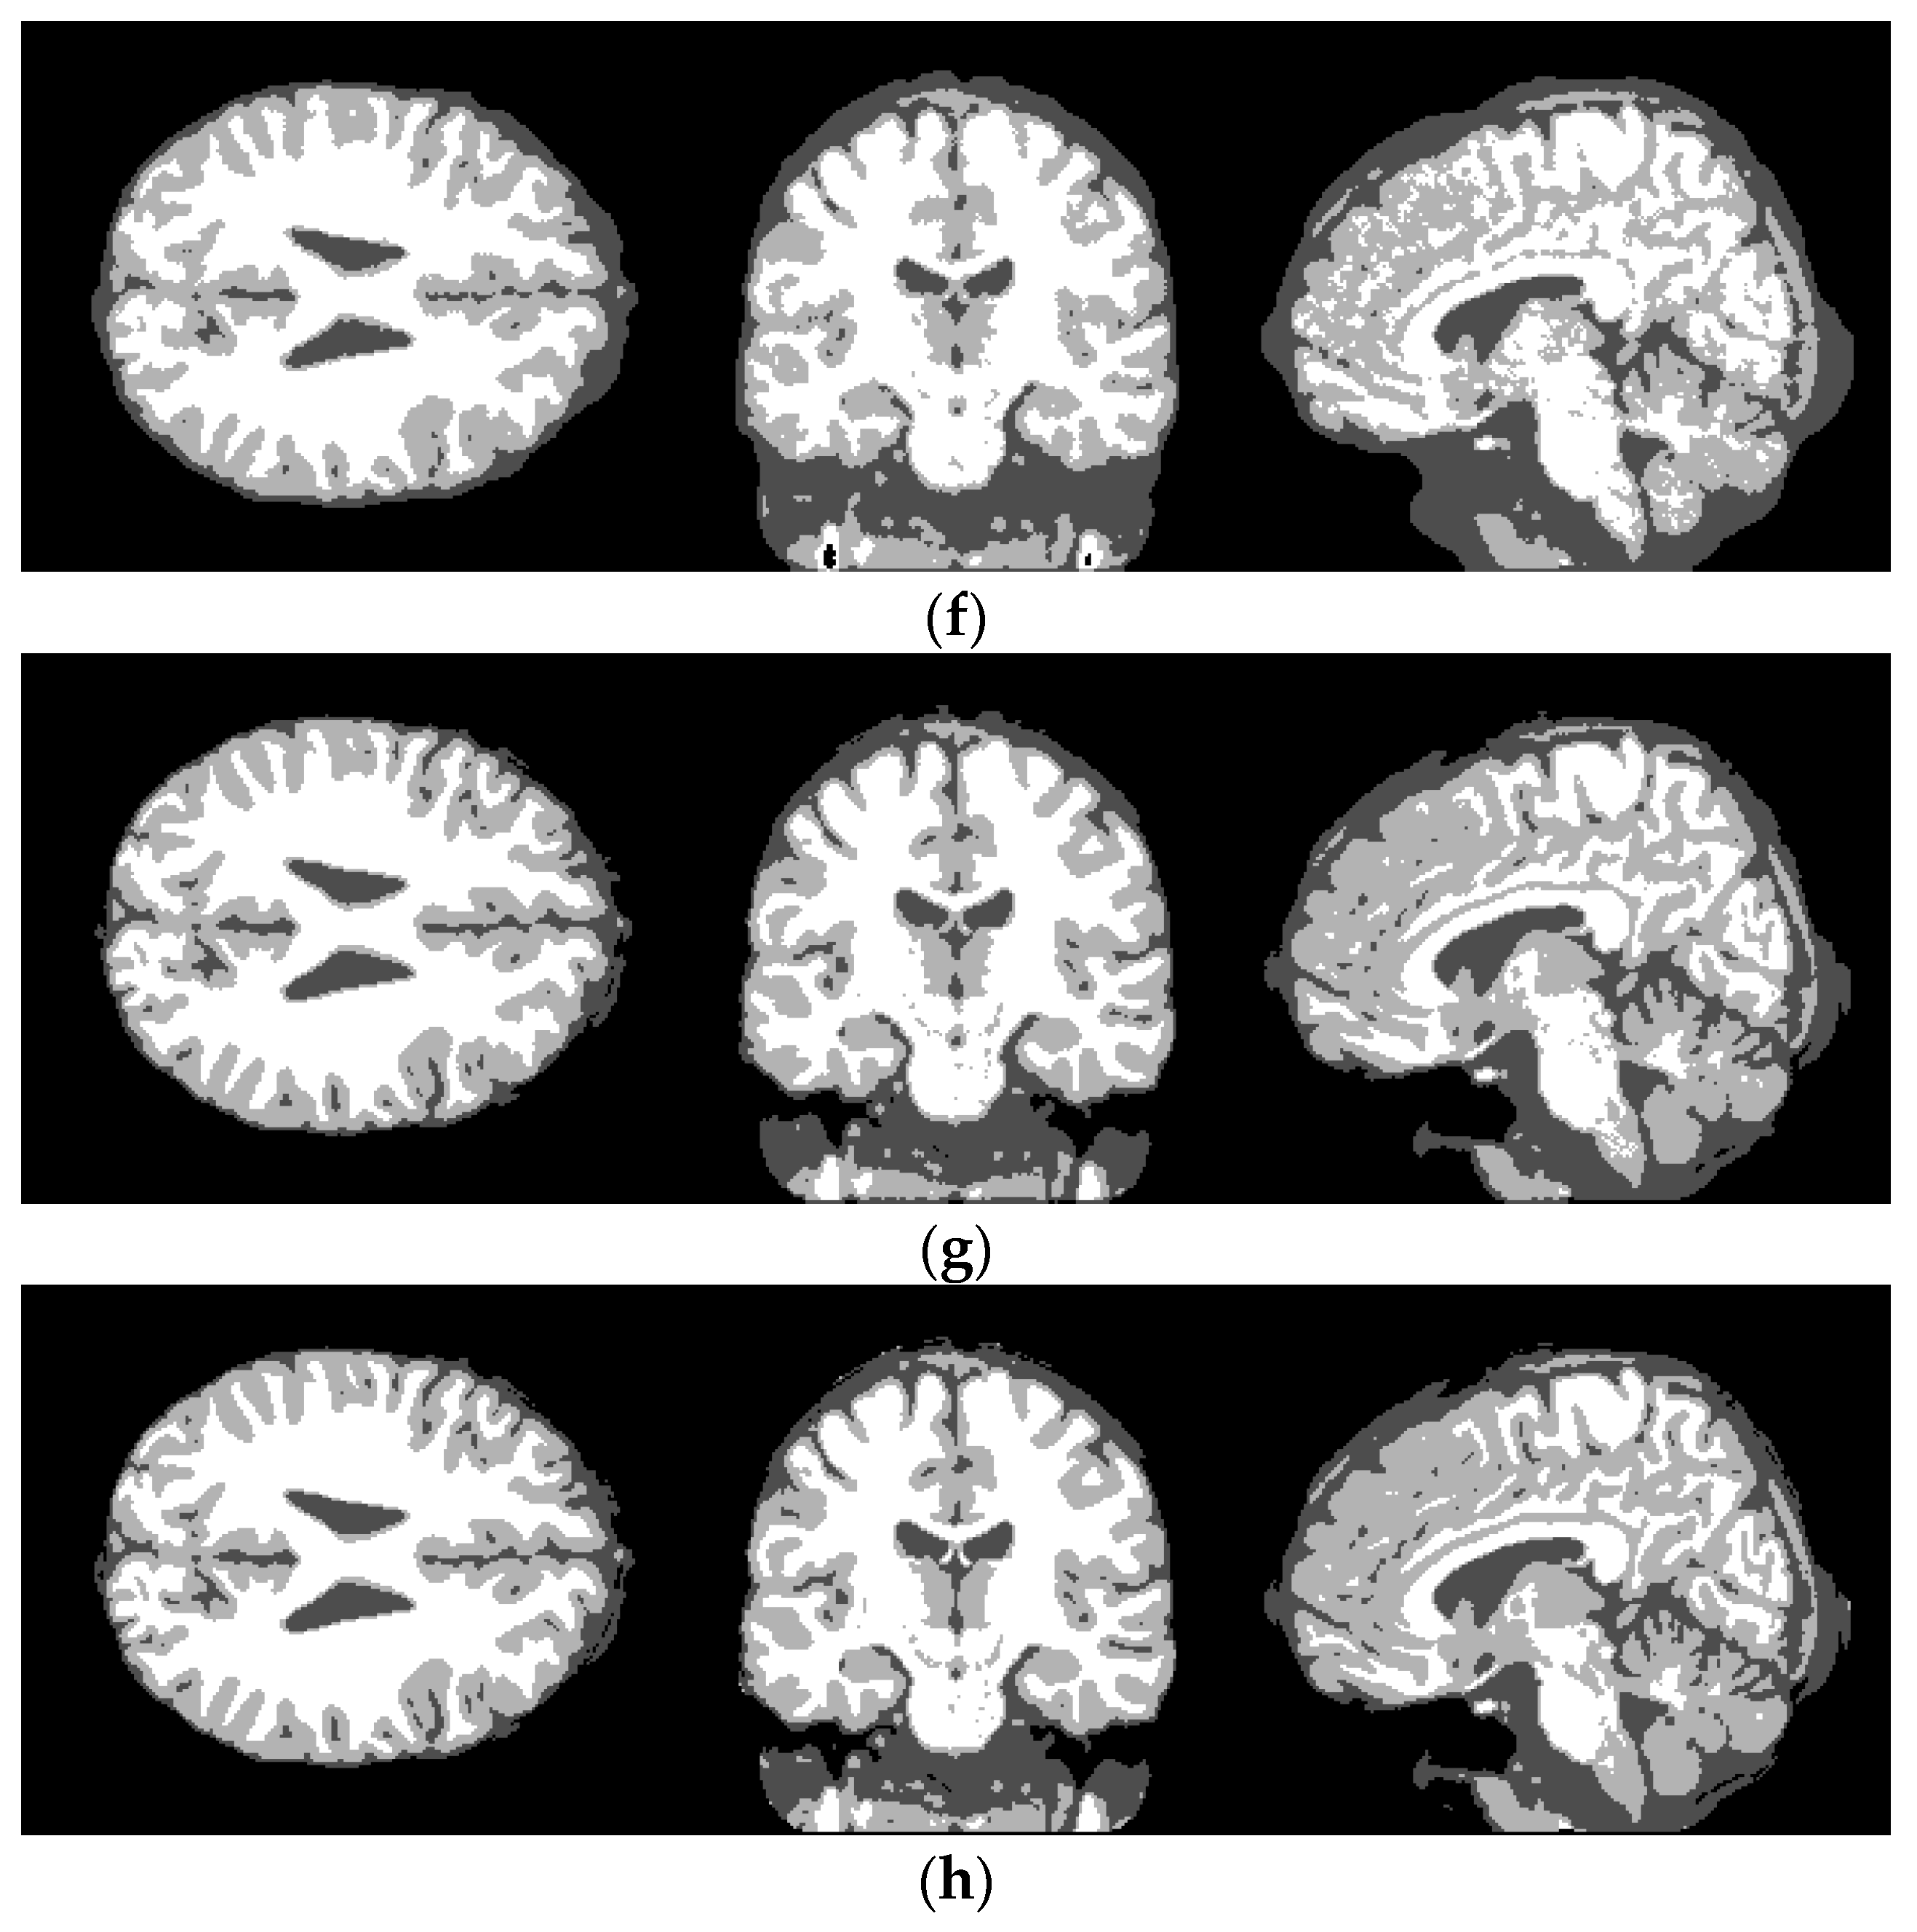

4.2. Simulated Brain MR Images